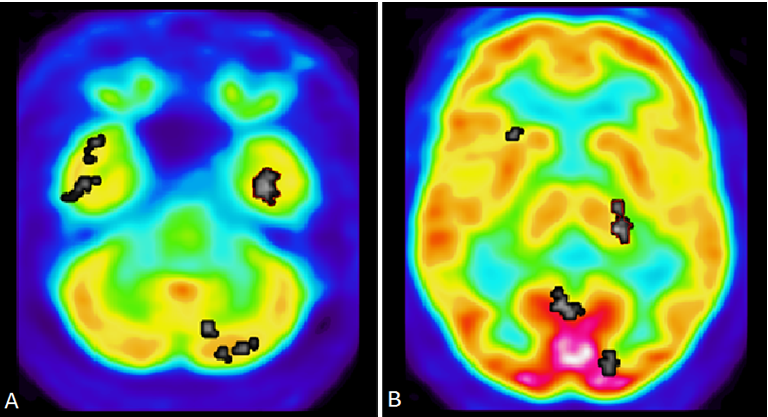

MRI-DTI analysis

Brain imaging assessments done with MRI Diffusion Tensor Imaging show significant abnormalities consistent with traumatic brain injury and high risk of chronic traumatic encephalopathy (Figure 4a). MRI-DTI findings found that the defendant displays very significant abnormal decreases in FA in the left anterior corpus callosum (mean FA ROI ratio is 0.37 whereas controls averaged 0.58, standard deviation=0.04, z-score= -5.38, p-score =, 7.6E-08). The decrease in FA in the mid corpus callosum is consistent with significant and multiple TBIs received in the past. He also has very significant abnormal decreases in the left internal capsule FA (mean FA is 0.25 whereas controls averaged 0.42, standard deviation = 0.02, z-score =-7.91, p-score =2.5E-15 (Figure 4b). The odds of this occurring by chance alone are 2.5 out of quadrillion.

Figure 4A, MRI-DTI findings found that the defendant displays very significant abnormal decreases in FA in the left anterior corpus callosum. B, Diffusion Tensor Imaging (DTI) Statistical Analysis. Left anterior corpus callosum and left internal capsule display high risk of CTE. Abnormal decrease in fractional anisotropy (FA) in left internal capsule consistent with traumatic brain injury. P-value 2.5E-15, indicated the chances of this occurring by chance is 2.5 out of a quadrillion.

Tractographic analysis shows that there is an asymmetrical decrease in fiber track length in the left middle corpus callosum compared to the right (Figure 5a) Decreased track fibers were found in DTI Tractography in the left hemisphere of the corpus callosum compared to the right hemisphere (Figure 5b). These DTI findings are predominantly left sided and would be consistent with left sided head trauma. They would also be consistent with his history of having been beaten in the head repeatedly by a right handed individual such as his abusive mother growing up. They would also be consistent with left side limbic kindling noted above in the PET scan analysis.

Figure 5A DTI-Tractography images in Corpus Colosseum, white fibers tract in left hemisphere is abnormal than right hemisphere. B Decreased fiber track length on the left side of the corpus callosum compared to the right side show lack of connectivity. Tractography suggest defendant for high risk of CTE and even Alzheimer’s disease.